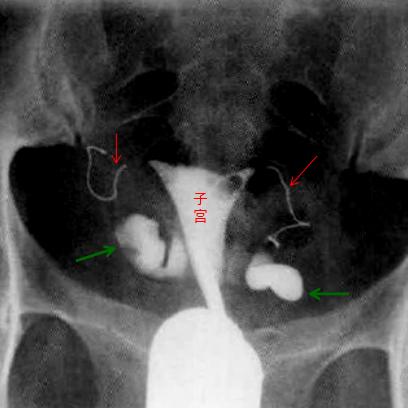

输卵管栓塞术中,红箭为栓塞物,绿箭为输卵管积水